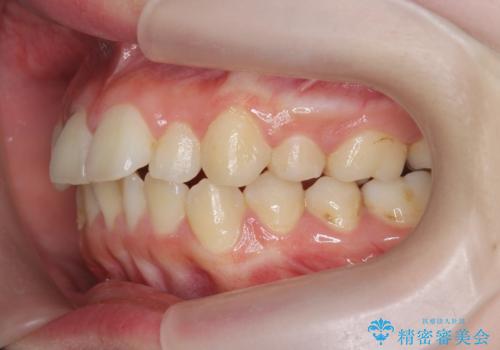

- 前歯の角度 奥歯の噛み合わせの改善をするために、矯正治療を希望され来院されました。

右側奥歯は上顎が相対的に前方に位置し(上顎前突)、そのため前歯の角度も突き出たようになり出っ歯のように見える状態でした。

マイクロインプラントを用いて、上顎奥歯を後方に移動させることで噛み合わせ・前歯の角度を改善していきます。